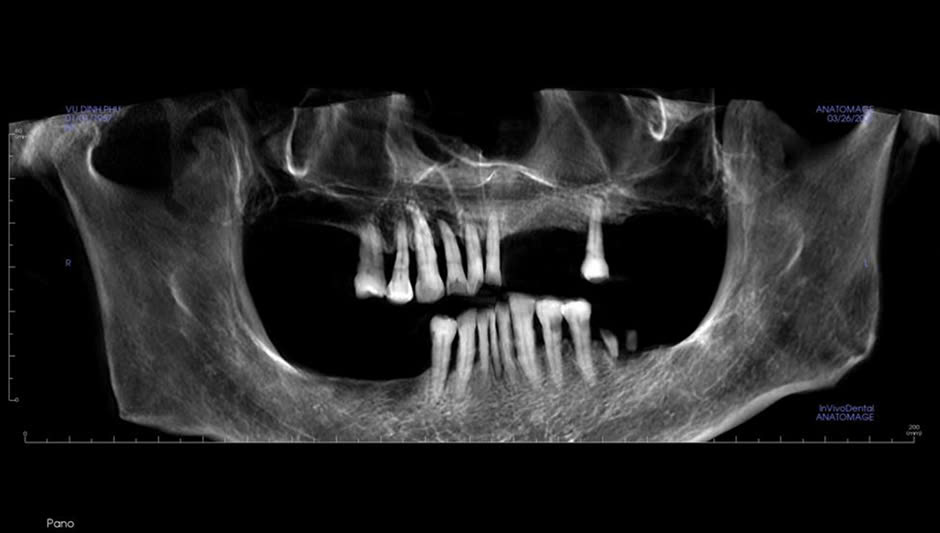

HIỂU VỀ VIÊM LỢI CẤP Ở TRẺ EM : CHA MẸ CẦN BIẾT GÌ?

Viêm lợi là một vấn đề răng miệng rất phổ biến ở trẻ em. Tuy nhiên, nhiều bố mẹ vẫn còn chưa nhận biết được các dấu hiệu ban đầu hoặc chưa biết rõ cách chăm sóc và phòng ngừa...